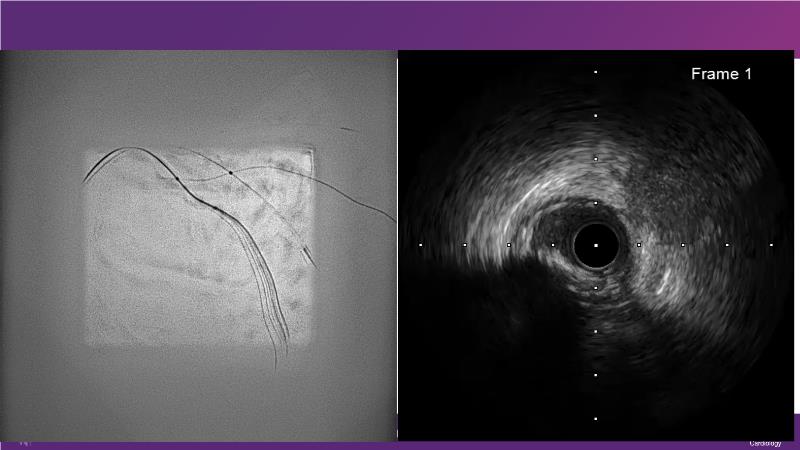

Cracking calcium: best practices to integrate intravascular lithotripsy into your calcium management algorithm

With this session, keep up to date on the evidence, trials and outcome data for intravascular lithotripsy in severely calcified lesions. Learn how to use this technique in real-world patients and understand its role in the treatment algorithm for severely calcified coronary lesions.

- To learn how to use intravascular lithotripsy in real-world patients with severely calcified coronary lesions